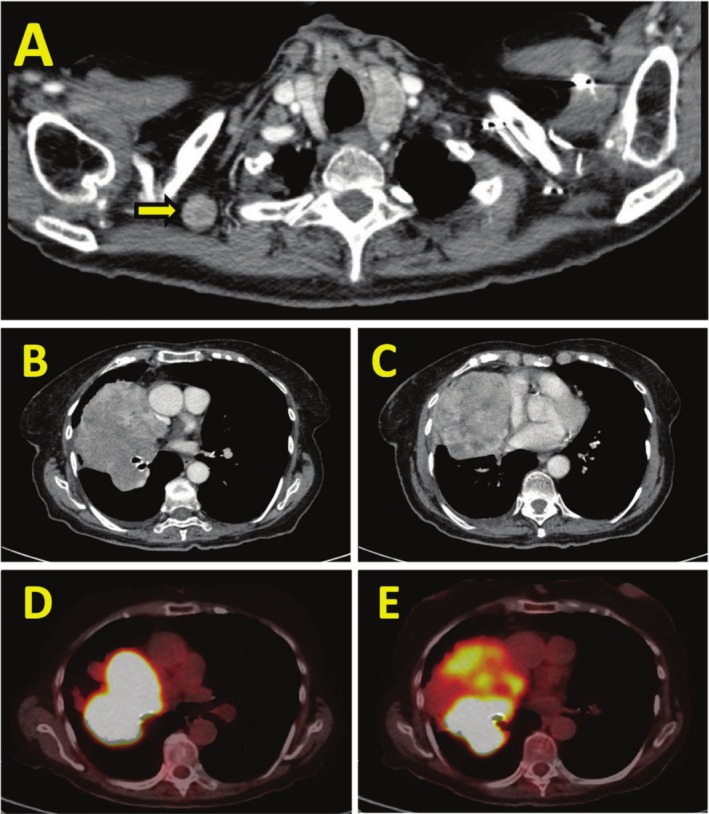

原发性肺平滑肌肉瘤是一种极为罕见的恶性肿瘤,占所有肺癌的不到0.5%。由于罕见,没有标准化的治疗指南。在被认为不能切除的病例中,预后尤其差。我们描述的情况下,一个90岁的妇女谁提出了进行性呼吸困难和咳嗽超过1个月。胸部计算机断层扫描显示一个大的右肺门肿块,延伸到右上叶和中叶,毗邻纵隔和心包膜。组织病理学分析证实为原发性肺平滑肌肉瘤。考虑到她的高龄和合并症,她不适合手术治疗。分子分析显示PDL1表达

Primary pulmonary leiomyosarcoma is an exceedingly rare malignancy, comprising less than 0.5% of all lung cancers. Due to its rarity, no standardised treatment guidelines exist. Prognosis is especially poor in cases which are deemed unresectable. We describe the case of a 90-year-old woman who presented with progressive dyspnea and cough over 1 month. Chest computed tomography revealed a large right hilar mass extending into the right upper and middle lobes, abutting the mediastinum and pericardium. Histopathological analysis confirmed primary pulmonary leiomyosarcoma. Given her advanced age and comorbidities, she was not a candidate for surgical intervention. Molecular profiling demonstrated PDL1 expression < 1% and no targetable mutations, ruling out the option of immunotherapy. She was managed with palliative radiotherapy followed by pazopanib therapy. Serial imaging demonstrated disease control, with an extended survival of approximately 5 years. Despite a median reported survival of 14 months, our patient achieved prolonged survival, highlighting the importance of an individualised therapeutic approach for elderly patients with rare malignancies.